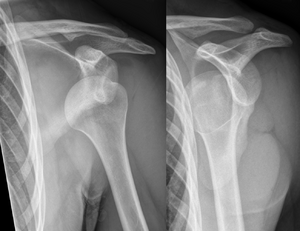

خلع أمامي للكتف الأيسر.

عادة ما يحدث خلع الكتف نتيجة لسقوط الشخص على ذراعه وهي ممدودة أو سقوطه على الكتف.[4] عادة ما يعتمد التشخيص على العلامات الظاهرة على الحالة ويتم التأكد عن طريق التصوير بأشعة إكس.[2] تصنف حالات خلع الكتف إلى خلع أمامي، خلفي، سفلي، وعلوي والأكثر شيوعاً هو خلع الكتف الأمامي.[2][1]

عادة ما يتم تشخيص خلع الكتف اعتماداً على التاريخ المرضي والفحص السريري لها. يتم عمل تصوير إشعاعي لتأكيد التشخيص. معظم حالات خلع الكتف التي تظهر في التصوير الإشعاعي تظهر اختلال في المفصل الحقاني العضدي. قد يكون من الصعب التحقق من انخلاع المفصل الخارجي عن طريق التصوير الإشعاعي الاعتيادي، لكن يتم اكتشافها بسهول عن طريق أعراض تشخيصية أخرى. بعد رد الكتف، عادة ما يكرر التصوير الإشعاعي مرة أخرى للتأكد من نجاح الرد وللوقوف على إصابات العظام. عند تكرار خلع الكتف، يستخدم التصوير بالرنين المغناطيسي لتقييم الأضرار التي لحقت بالأنسجة الناعمة. فيما يتعلق بتكرار خلع الكتف، يعتبر اختبار الترقب (عدم الاستقرار الداخلي) وعلامة سولكوس (عدم الاستقرار الخارجي) من الوسائل المفيدة للوقوف على استعداد الحالة للإصابة بخلع الكتف مستقبلياً.